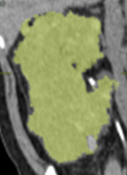

●当院では腎臓の大きさを正確に測定するための3次元画像解析システムVINCENTを導入しており、年々の変化や治療効果を評価することが可能です。

VINCENTでCTから腎臓の大きさを測定します。